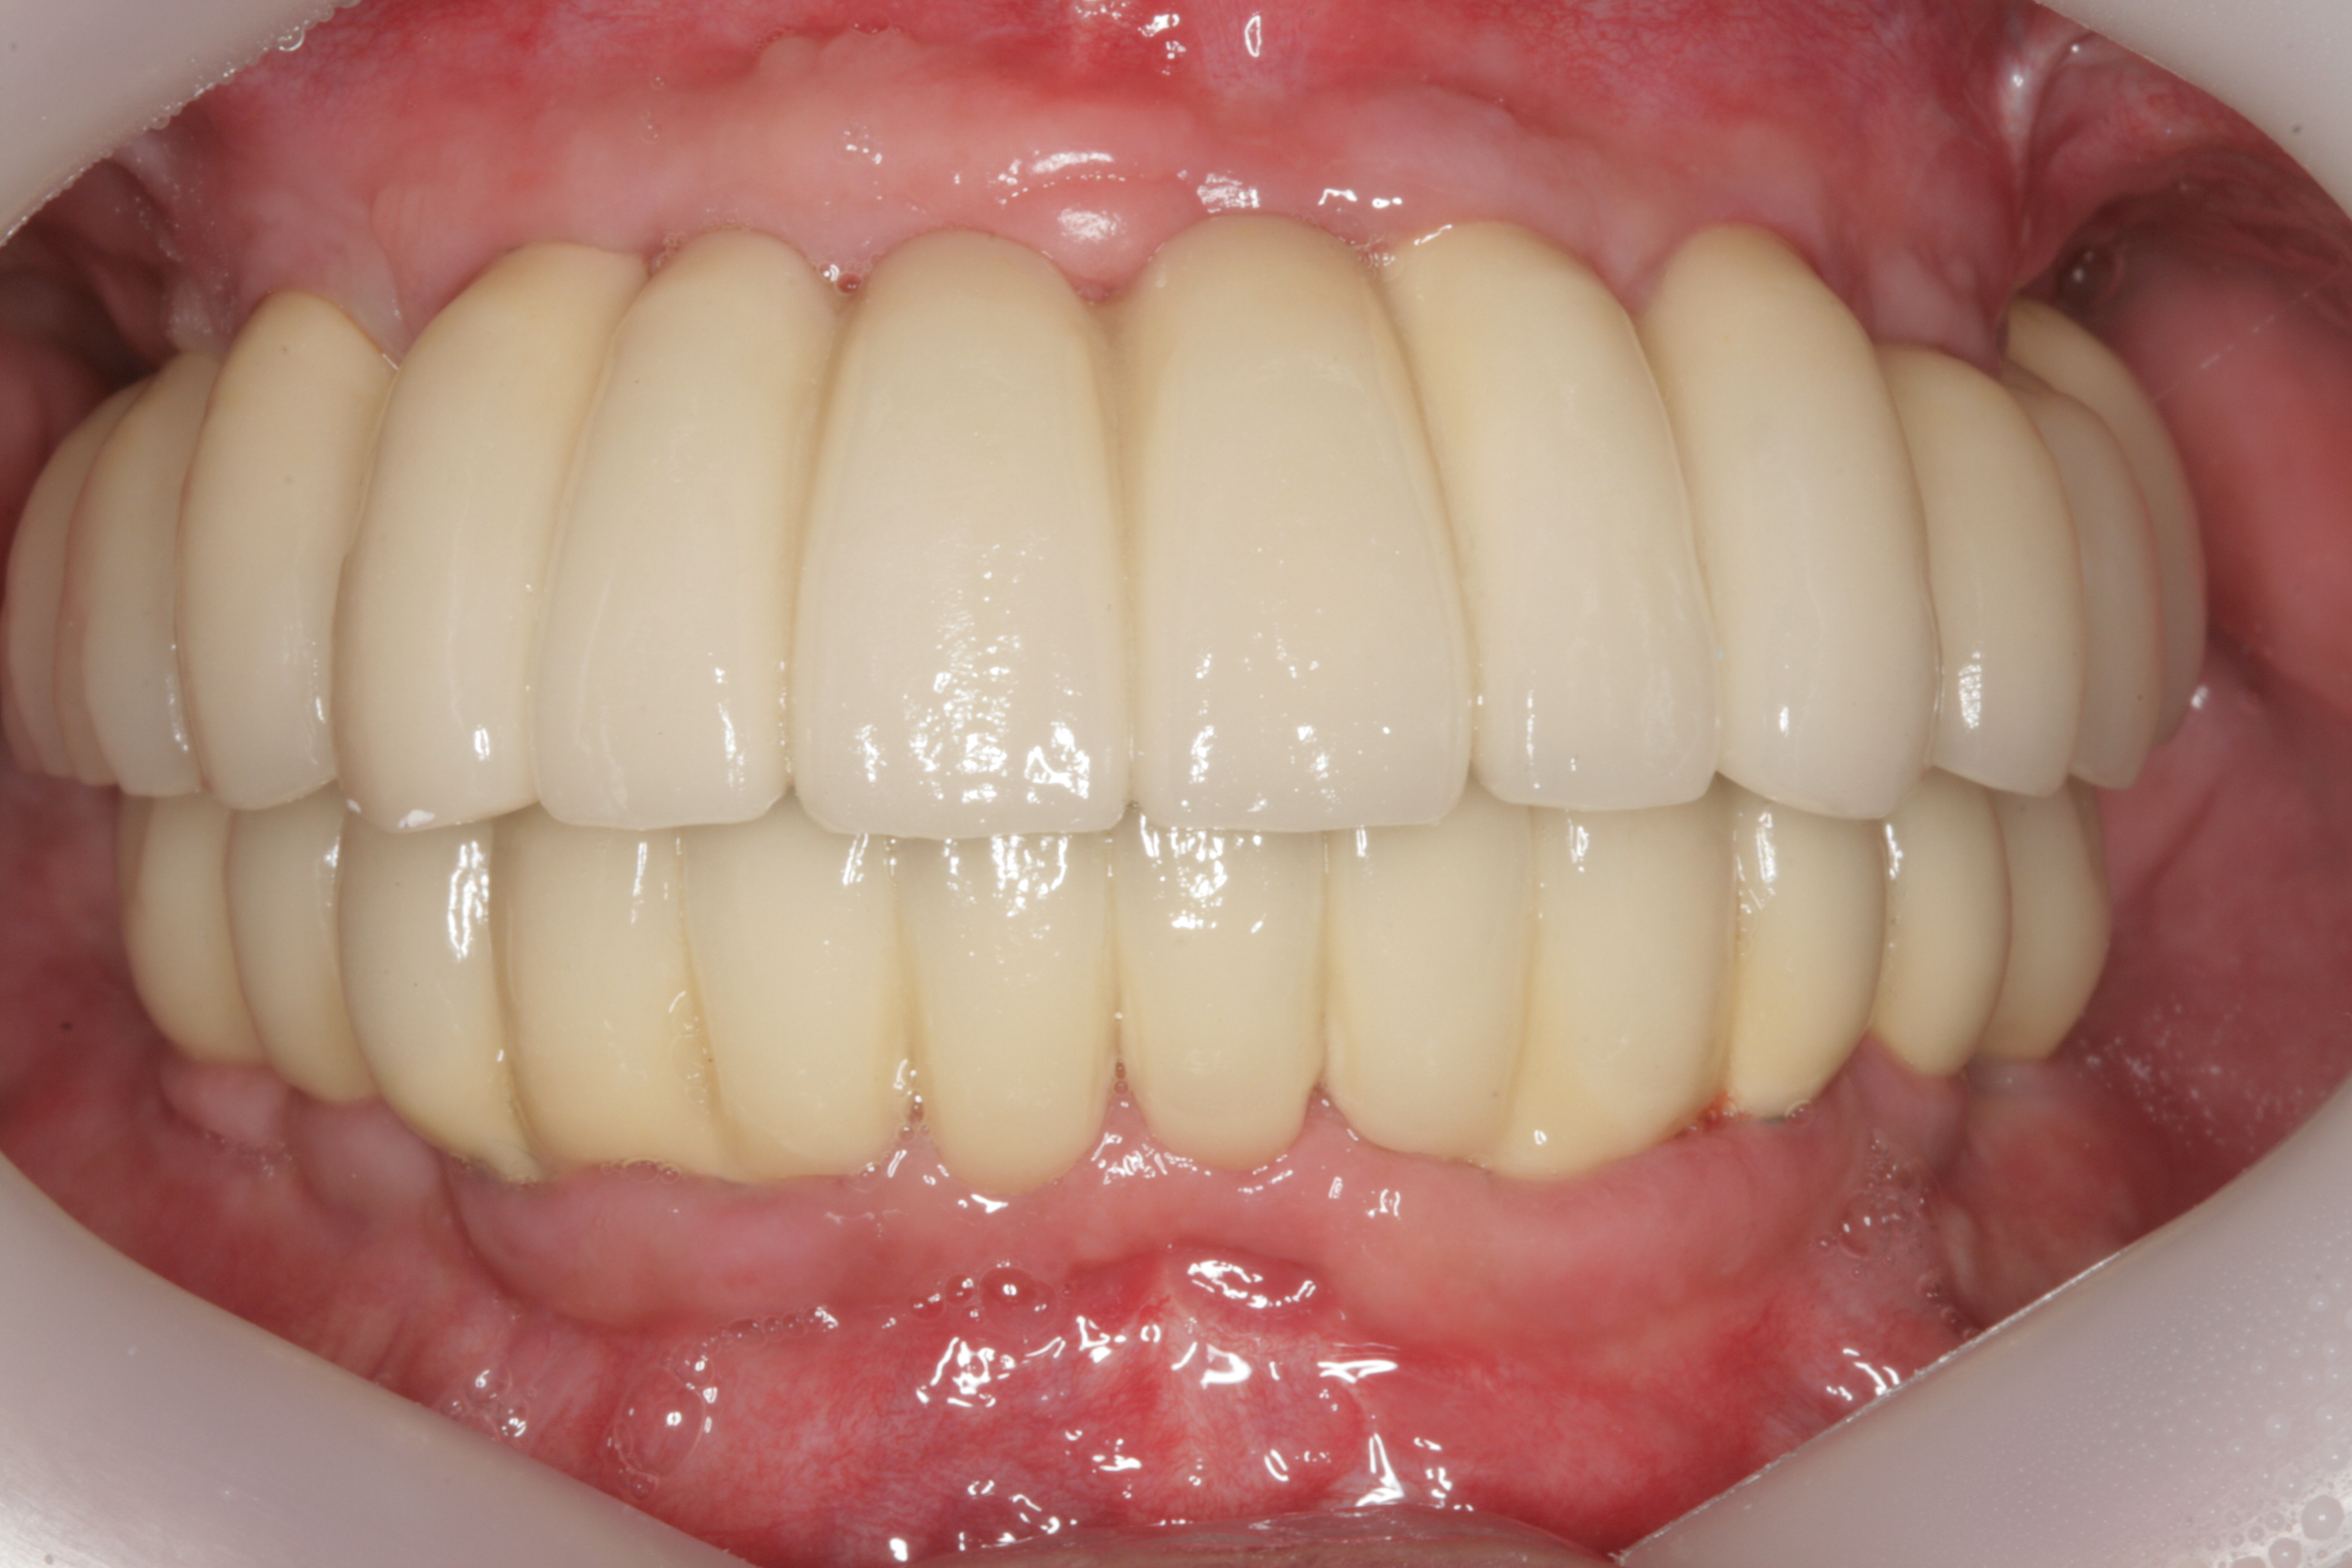

최종 보철물까지 올리고 난 후 구강 내 사진입니다.

평상시의 교합 뿐만아니라 좌우로 아래턱을 크게 움직였을 때도 불편함이 없습니다.